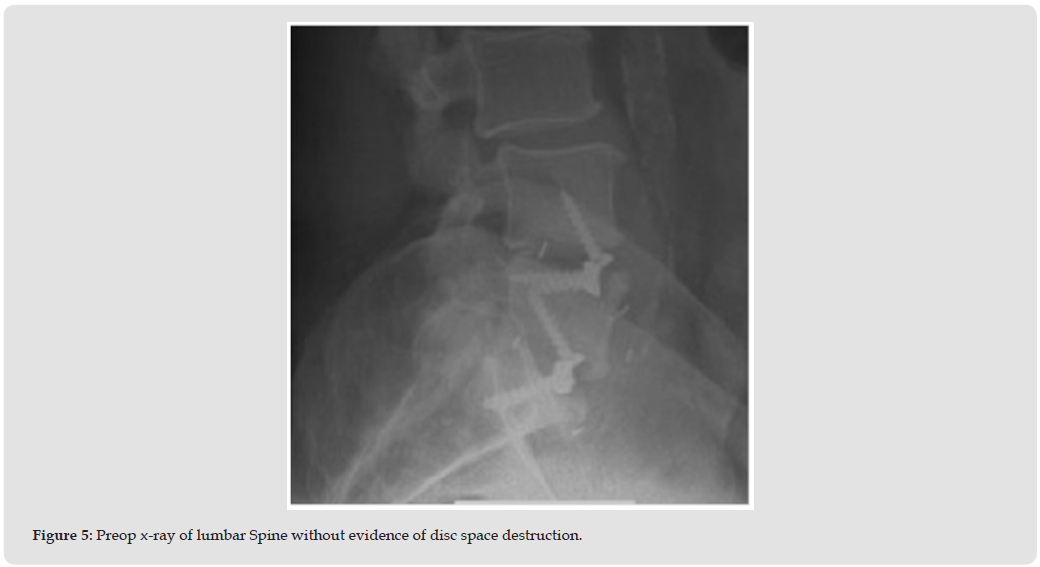

The patient is a 64-year-old male with a history of diabetes mellitus and previous L4-S1 spinal fusion surgery. He presents with intractable back with inability to stand and ambulate independently. The patient has severe bilateral anterior thigh pain and anterior leg pain radiating to the feet. He is ambulating with a kyphotic gait and exhibits weakness with quadriceps extension bilaterally measuring 4/5 on manual muscle testing. The L3-4 disc space degeneration was not seen on radiographs from 6 months prior (Figure 5). Preoperative CT (Figures 6a & 6b) immediately preceding surgery exhibits bony destruction at L3-4 with endplate irregularities and listhesis, which is a dramatic change compared to his radiographs. The patient was indicated for an L3 corpectomy with T10- pelvis fusion for decompression and stabilization. L3 corpectomy with long-segment fixation from T10–pelvis was performed and a titanium expandable cage at L3 was placed and was filled exclusively with (Osteoflo® Hydrofiber). Intraoperative cultures to rule out infection as a cause of his bony destruction were obtained. The intraoperative cultures eventually grew Pseudomonas aeruginosa. Postoperative x-rays (Figures 7a & 7b) showed appropriate spinal alignment and CT at 6 months after surgery had fusion through the corpectomy cage (Figures 8a & 8b).